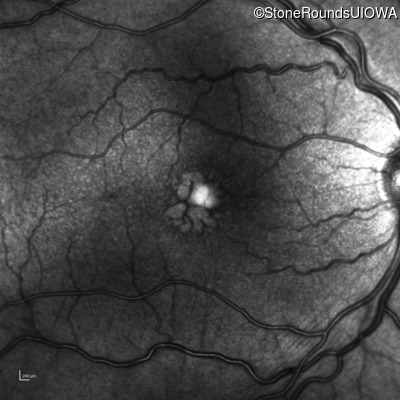

Infrared Fundus Photograph - Left - 20/40

Exemplar